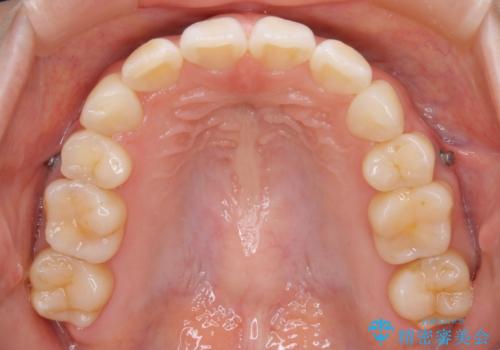

- 以前、中学生から高校生にかけてワイヤー装置による抜歯矯正を経験されている患者さんで、大人になってからのライフスタイルの変化でリテーナーを継続使用することができず、ガタつきが目立つようになってきてしまったのでもう一度矯正治療がしたいという主訴でご来院されました。

既に上下左右の4番目の歯が抜歯されているため、今回の治療では抜歯をせず歯の移動だけでガタつきを治す必要があり難易度が高くなっていました。